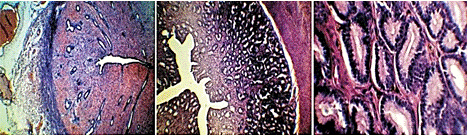

Анэструс в этот период яичники малоактивны. Рост фолликулов носит абортивный (незавершенный) характер. Третичные фолликулы на разных стадиях своего развития подвергаются атрезии. Идет активный лизис желтых тел предыдущего полового цикла. В эндометрии происходит восстановление (регенерация) эпителиального покрова. Железы эндометрия выглядят ровными трубочками, эпителий желез представлен кубическими клетками, но объем ядер этих клеток значительно превышает объем цитоплазмы (рис. 4).

Течка - процесс выделения слизи из половых органов самки. В этом период в матке начинаются процессы пролиферации. Количество желез не становится больше, но они начинают извиваться, срез проходит несколько раз через одну и ту же железу, создавая видимость их увеличения (рис. 5).

Эпителий желез из кубического, становится цилиндрическим. В периоде пролиферации можно выделить раннюю, среднюю и позднюю стадии. На ранней стадии в призматическом эпителии маточных желез ядра расположены в один ряд вдоль базальной мембраны (рис. 6).

В среднюю стадию пролиферации эпителий маточных желез становится псевдомногорядным, ядра эпителия находятся на разных уровнях (рис. 7). И, наконец, в позднюю стадию ядра эпителия желез выстраиваются в один ряд вдоль апикальной мембраны клеток (рис. 8).

Далее пролиферирующий эпителий эндометрия превращается в секреторный. И наступает гестагеновая фаза, которая может быть разделена на три периода ранний, промежуточный и поздний. В ранний период секреторной фазы ядра эпителиальных клеток маточных желез находятся возле парабазальной мембраны, но под ними образуется большое количество вакуолей. Затем вакуоли перемещаются к апикальной мембране и вытесняют ядра к базальной мембране. Они вновь выстраиваются в один ряд вдоль базальной мембраны. Но апикальный край желез уже не такой ровный, через него начинается секреция. Просвет желез расширяется, в нем обнаруживается секрет маточных желез (рис. 9).

На пике активности маточных желез в среднюю стадию фазы секреции клетки маточных желез становятся больше похожи на кубические, в просвете желез много секрета, ядра занимают центральное положение в клетке (рис. 10). Наконец в позднюю стадию секреции, при не наступившей беременности активность желтых тел начинает снижаться, и клетки желез становятся уплощенными, но еще продолжают секретировать, секрет обнаруживается в просвете желез (рис. 11). По мере снижения прогестероновой активности секреторные процессы в них затухают, и эндометрий подвергается обратному развитию, постепенно принимает вид, показанный на рис. 12, 13. Железы еще имеют много извилин, просвет их расширен, но эпителий в них плоский. Резко снижается клеточность стромы эндометрия. Затем эндометрий принимает первоначальный вид (рис. 4, 5).